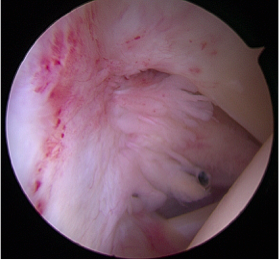

What does it look like inside?

The image below on the left shows a keyhole (Arthroscopic) view of the inside of a normal shoulder.  The rotator interval (labelled) is an area of exposed capsule that lies between the subscapularis and long head of biceps tendons at the front of the shoulder.  You can see in this normal shoulder that this capsule in the rotator interval is thin and almost translucent.  Compare this to the right hand image.  This is the same view, but this patient has a frozen shoulder. You can see that the rotator interval is thickened, inflamed and contracted.  This contraction is affecting the capsule around the whole joint and 'incarcerating' the shoulder.